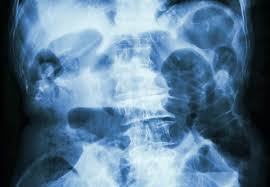

• X-ray of the abdomen

انسداد روده 3